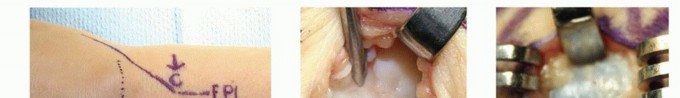

Accurate diagnosis relies heavily on a thorough history and physical examination. Transillumination is a simple, highly effective bedside test; ganglion cysts will brilliantly transilluminate, whereas solid tumors like GCTTS or keratin-filled EICs will not. Advanced imaging is not routinely required for classic presentations but is invaluable for atypical masses, recurrent lesions, or when preoperative planning requires precise mapping of neurovascular structures.

Clinical & Radiographic Imaging Archive